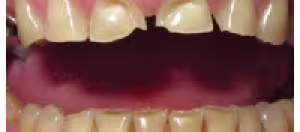

Dental erosion occurs primarily due to the excessive presence of non-bacterial extrinsic acids (especially dietary acids such as acidic drinks), as well as intrinsic gastric acid associated with gastroesophageal reflux disease (GERD) and bulimia (Moazzez et al. 2004; Bouqot & Seime 1997). Dental erosion involves the demineralization and softening of the tooth surface, which once softened, is highly susceptible to abrasion and attrition (Figure 7). A diagnosis of erosion can be made based on the pattern of surface loss of enamel and/or dentin (Figures 8a,b)

Figure 8a. Generalized erosion

Courtesy of Prof. Ian Meyers

Figure 8b. Severe palatal erosion and loss of tooth structure.